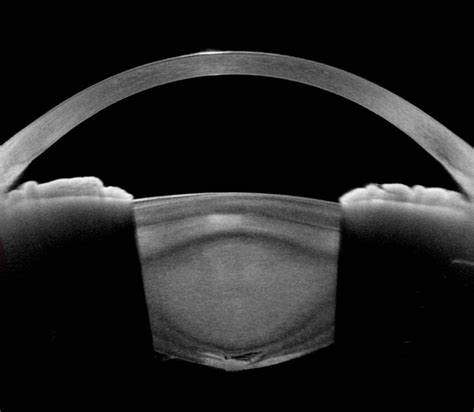

MICS PHACO EMULSIFICATION

PREMIUM INTRAOCULAR IOL IMPLANTATION

MULTIFOCAL, ADVANCE MONOFOCAL, TRIFOCAL IOL IMPLANTATION

SCLERAL FIXATED IOL IMPLANTATION

ANIRIDIA IOL IMPLANTATION